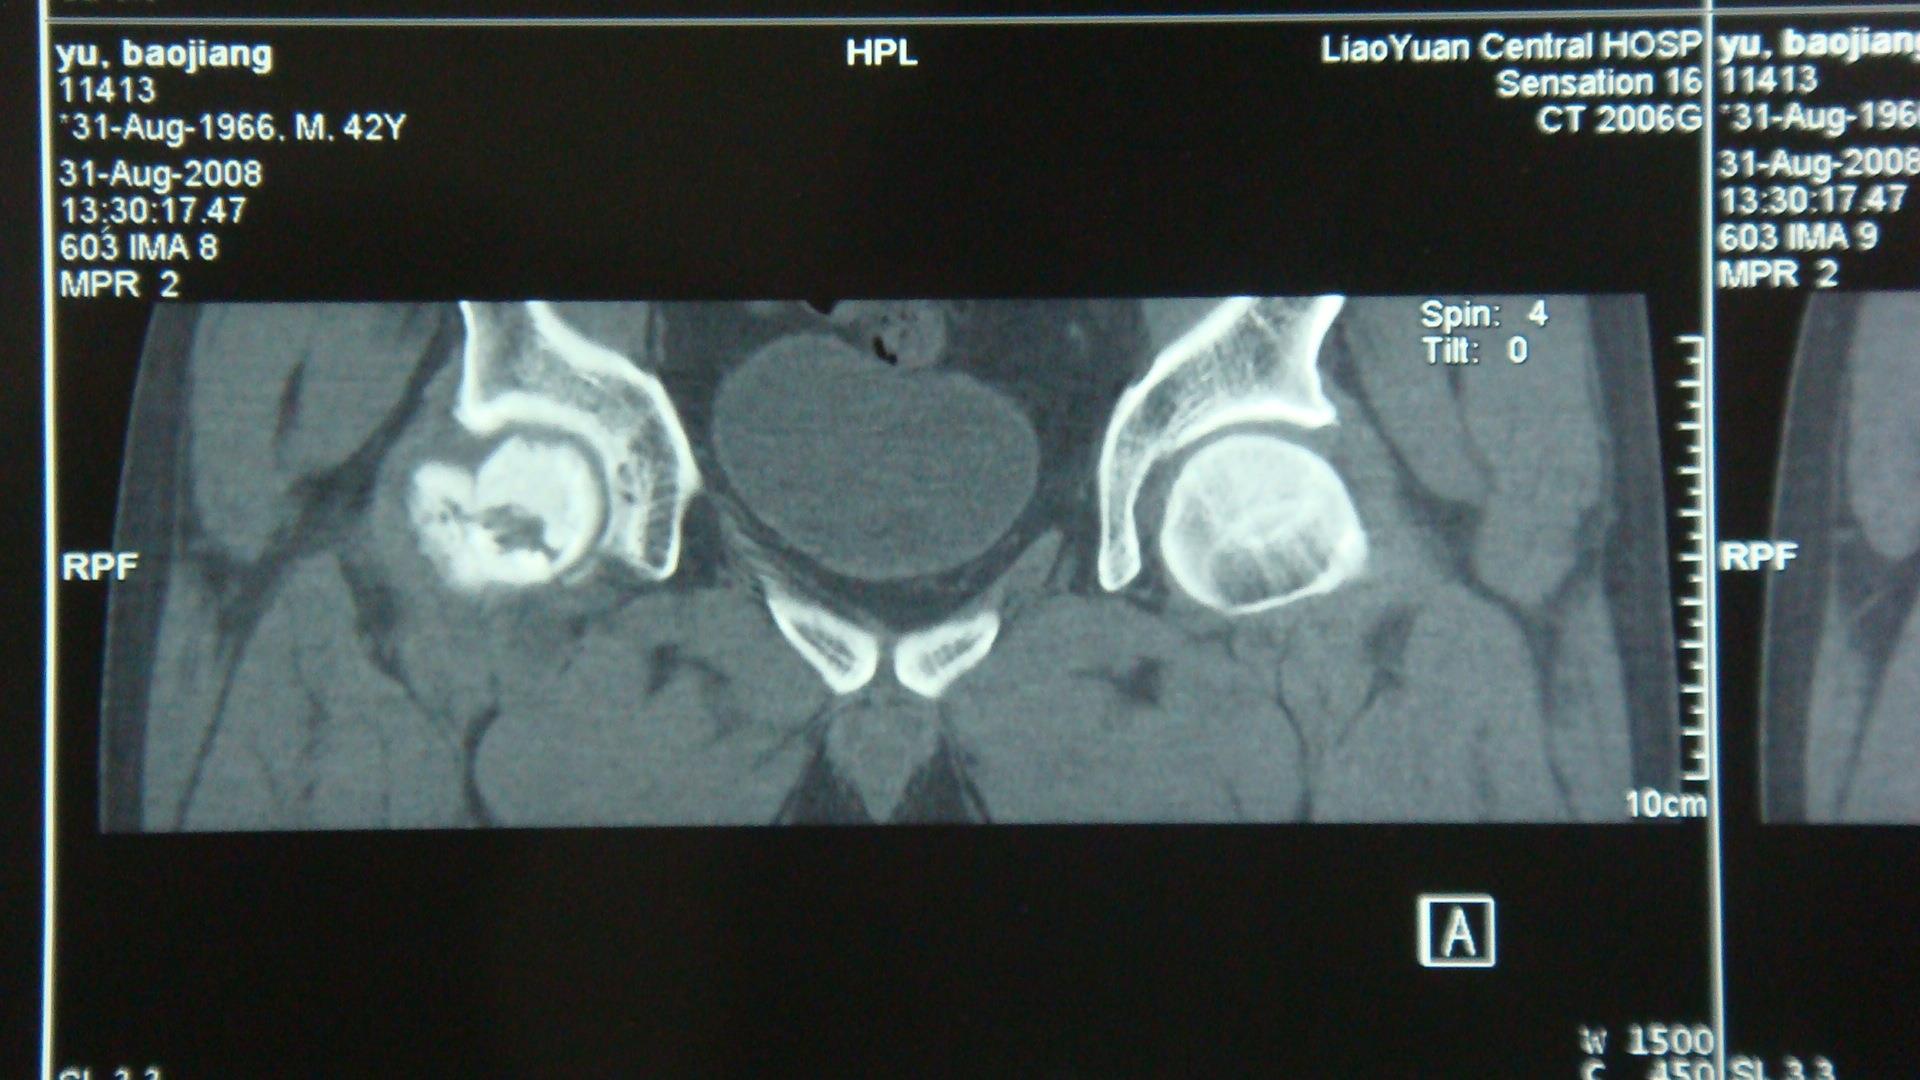

双侧股骨头X光片,CT片表现:左侧股骨头、髋关节形态正常,未见异常密度影,右侧股骨头无菌性坏死多年后,外伤(此次)见右侧股骨头变扁,密度增高,其内见多发囊变,并可见一侧股骨头下骨折线(CT明显),轻度成角,关节间隙大致正常。外伤前(2007-9-8)CT片未见明显横行骨折线。诊断:1、右股骨头无菌坏死后外伤,伴股骨头下骨折。2、左股骨头未见异常。

于某2008年8月27日外伤后CT片可见右股骨头下横行骨折线,而该患此前(2007年9月8日CT片)存在右侧股骨头无菌性坏死并有囊性变,但未见有骨折线。股骨头无菌性坏死又叫股骨头缺血性坏死或股骨头坏死。此病的发病机理为在多种原因的刺激下,股骨头的骨骺发生坏死,其内部生长的肉芽组织代替了原来的死骨,最终导致股骨头因密度变大而发生塌陷。因为骨质的变化,病变部位在轻微外力作用下即可发生骨折改变。因此,综合分析,如其在此期间(2007年9月8日至2008年8月27日)未受过其他外力,则考虑其右侧股骨头下骨折系此次外伤诱发所致。根据相关的鉴定原则,本案例适用间接因果关系类:是指外界各种致伤因素作用于人体患病组织、器官,在正常情况下不至于引起组织、器官解剖学结构连续性、完整性破坏及功能障碍,而在有器质性病变的基础上,使业已存在的器质性病变显示、加重。本案即是在患者原有股骨头坏死的疾病基础上,由外力诱发而形成骨折。

于某2007年9月8日影像学片

于某2008年8月27日影像学片